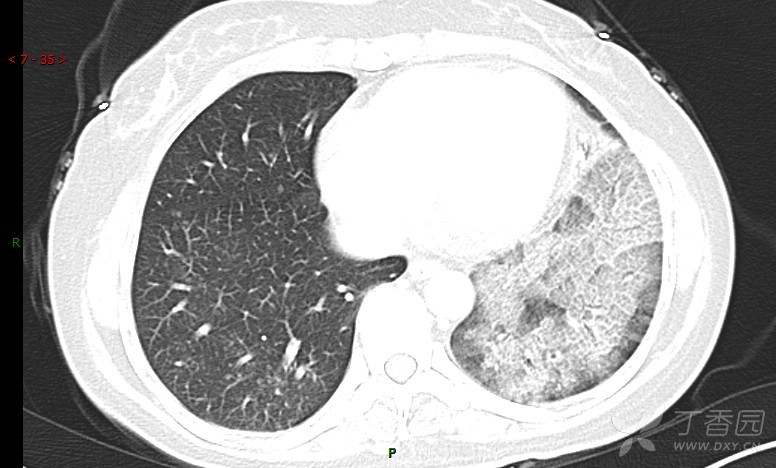

腺泡结节影,蜂窝征,这些都在提示……(病例3连发,附其他2例链接,病理已公布)

咳嗽1年余,加重7天。

患者于1年余前始受凉后出现咳嗽,多为干咳,未在意,未到医院就诊。近3月患者出现咳痰,多为黄色粘痰,量大,伴乏力,偶有头晕、心慌,无发热、胸痛、憋喘,无低热、盗汗、咯血、胸痛,无头痛,无恶心、呕吐、腹痛、腹泻,无尿频、尿急、尿痛,在当地诊所给予抗感染等对症支持治疗(具体药物及剂量不详),症状仍时有反复。患者于1月余前到外院就诊,行胸部CT提示双肺炎症,左肺重,考虑为“间质性肺炎”,给予“左氧氟沙星、利巴韦林、头孢哌酮舒巴坦钠注射液”治疗,复查胸部CT示病灶吸收不理想,后出院继续于诊所对症治疗(具体药物及剂量不详),效果欠佳。7天前患者无明显诱因出现上述症状加重,为求进一步诊治,特来我院就诊,我院门诊以“肺炎(重症)?”收入留观室,留观室给予“盐酸莫西沙星氯化钠”等对症治疗后,今日转入我科。患者自发病以来,神志清,精神差,饮食正常,睡眠增多,大小便正常,体重近3月减轻5公斤余。